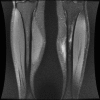

Results: Leg pain in athletes can be caused by many conditions, with the most frequent being medial tibial stress syndrome; chronic exertional compartment syndrome, stress fracture, nerve entrapment, and popliteal artery entrapment syndrome are also considerations. Conservative management is the mainstay of care for the majority of causes of chronic lower leg pain; however, surgical intervention may be necessary.